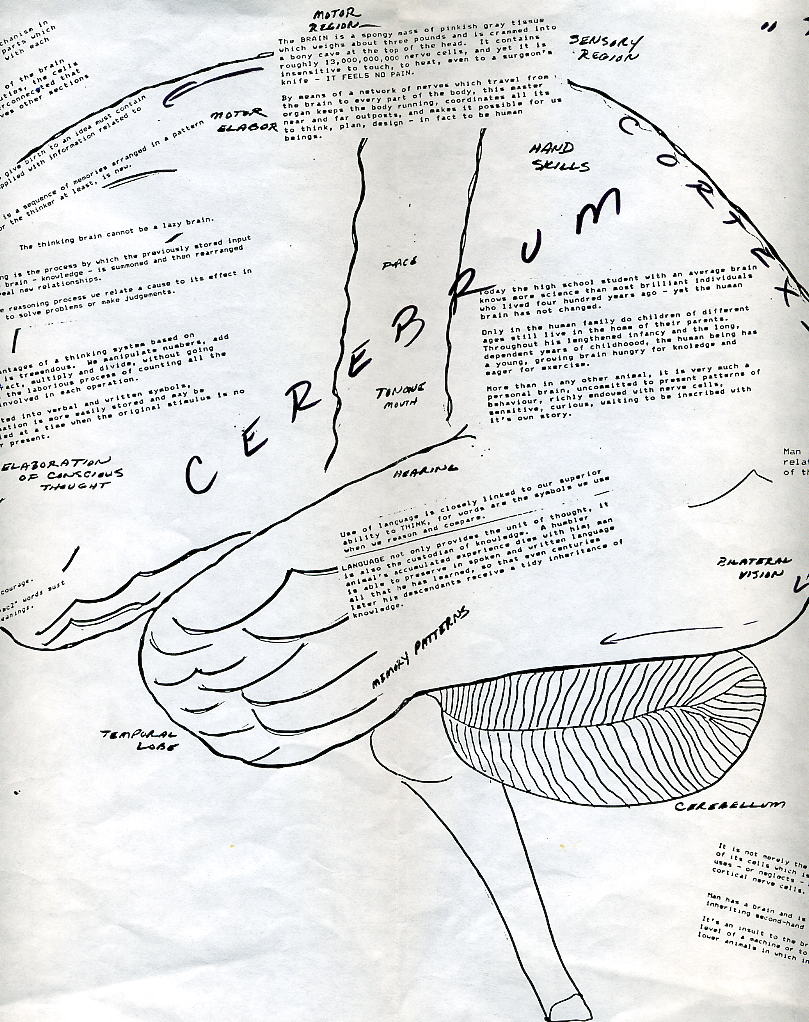

I THINK THEREFORE I AM

(Man has a brain and is expected to use it)